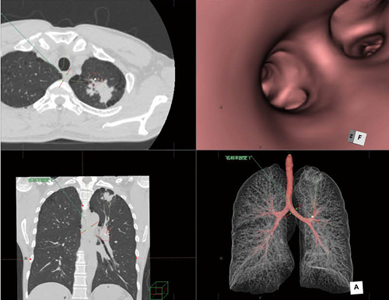

同院では、急性の心疾患に対しては心臓CTを実施し、ziostation2のCT冠動脈解析2を用いて主要3枝の抽出、Angio Graphic ViewやCPR、MIPなどの解析を行い、搬送時には画像および解析結果を保存したCDを作成してデータを提供している。安田主任は、心臓CTの解析におけるziostation2の運用について、「処理能力の向上はもちろんですが、ネットワーク型になったことで至適フェーズを特定してから、冠動脈の解析作業を手分けして行えるようになり、処理時間が大きく短縮しました。また、冠動脈解析についてもバージョンアップによって中心線の抽出精度が向上しており、精度の向上と時間の短縮に繋がっています」と評価する。実際にバージョンアップ以後、心臓CTの検査数が増加し、導入後の2か月間で前年と同数の検査を実施したとのことだ。

ネットワーク型となったことで複数の端末で並行に処理が可能になり、3D作成業務が効率化されたことを安田主任は高く評価する。また、本田医長は、内視鏡室や透視撮影装置に端末を設置したことで、手技前に病変や関心領域の情報を確認して進められることや、患者さんへの説明などでメリットがあるという。透視撮影装置では、気管支鏡検査や生検の際に、ziostation2の“CT肺野・気管支測定”で作成した気管支の3D画像を利用して、病変の事前確認やナビゲーションなどに利用している。

CT冠動脈解析による冠動脈スクリーニング

CT肺野・気管支測定による気管支VRの作成